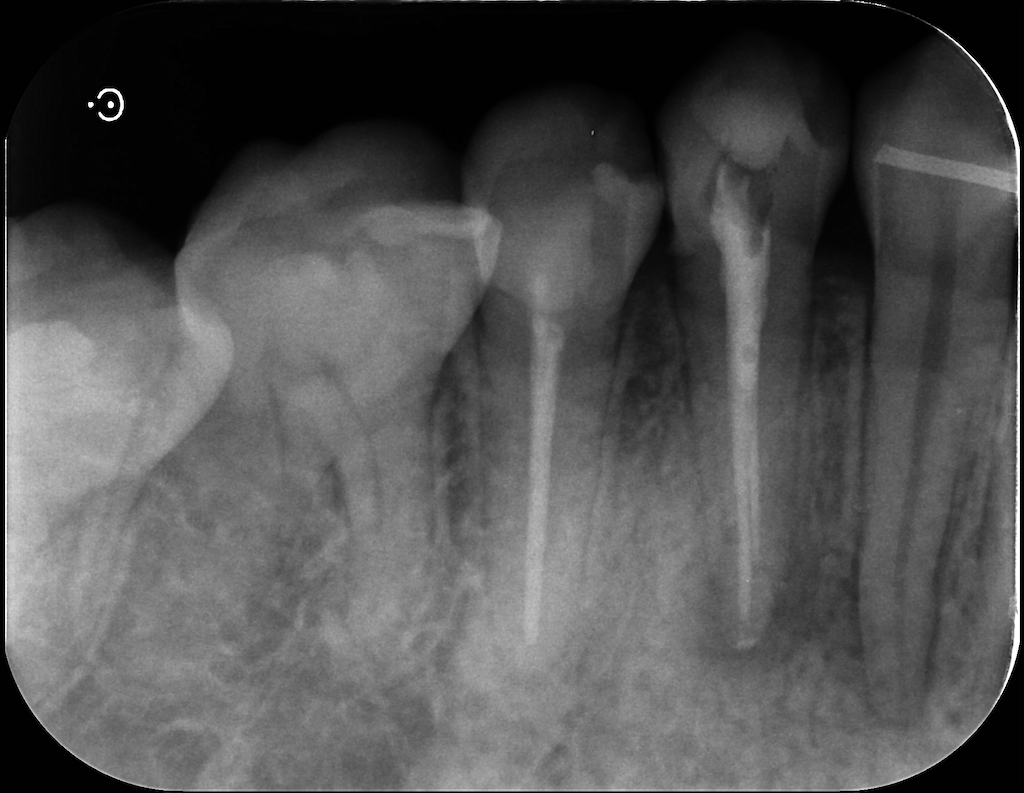

こちらは根充後のレントゲン。

次回は築造、レジンでおしまいです。(その後は経過観察ですね)

心なしか初診時の写真の時より、透過像が小さくなっているような気がします。